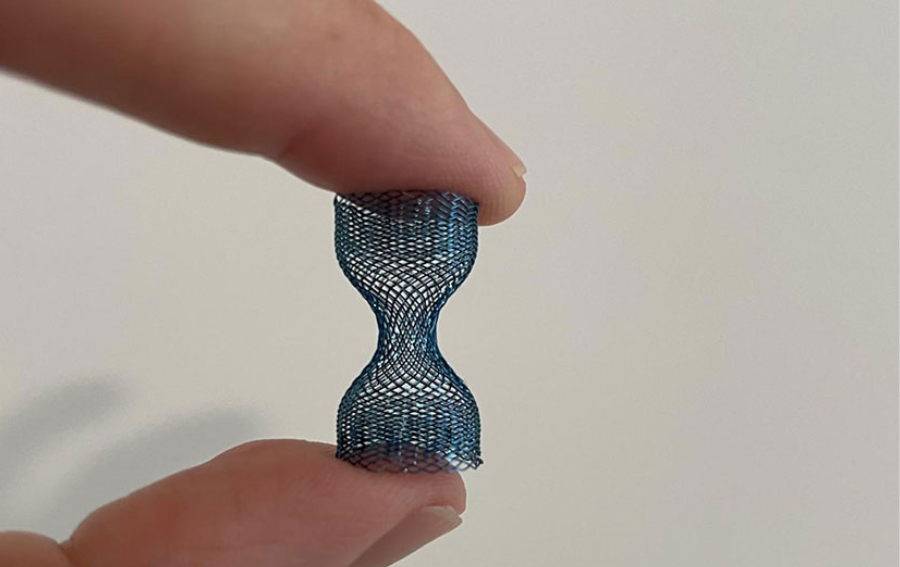

W Klinice Kardiologii UCKWUM przeprowadzono pierwszą w Polsce implantację nowego, samorozprężalnego reduktora przepływu do zatoki wieńcowej A-Flux Vahaticor. Jednocześnie był to pierwszy na świecie zabieg implantacji tego urządzenia u pacjentki z dławicą oporną w przebiegu choroby mikrokrążenia wieńcowego. Urządzenie to pozwala na zwiększenie tzw. całkowitej rezerwy wieńcowej, co stwarza szansę na poprawę jakości życia u chorych z nasiloną dysfunkcją mikrokrążenia, u których uporczywe dolegliwości w klatce piersiowej utrzymują się pomimo optymalizacji farmakoterapii. Reduktor przepływu jest urządzeniem, wszczepianym w znieczuleniu miejscowym, który po implantacji doprowadza do stopniowego przekrwienia uprzednio niedokrwionych obszarów serca. Konstrukcja nowoczesnego urządzenia A-Flux Reducer System pozwala na jego wcześniejsze pokrycie śródbłonkiem, czyli szybsze gojenie się naczynia po implantacji i tym samym wcześniejsze uwolnienie od objawów dławicy.